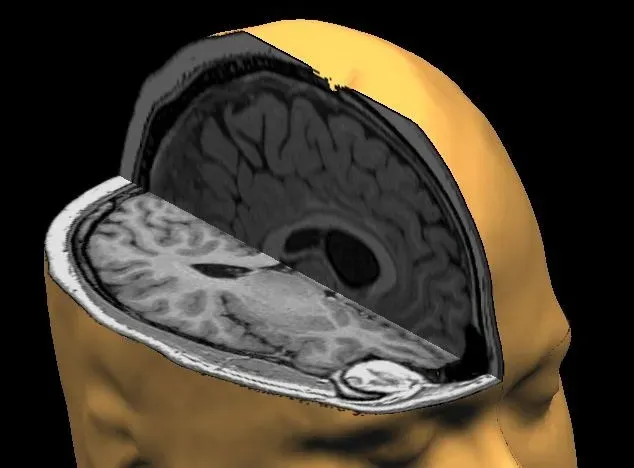

8. Memory Loss May Be More About Access Than Destruction

For decades, conditions like Alzheimer’s disease and other dementias were framed mostly as the irreversible death of neurons and loss of stored information. While cell loss is still a big piece, new work suggests that in some cases, memories may persist in damaged networks but become inaccessible. Animal studies have shown that when researchers artificially stimulated specific memory engrams in models of early-stage memory impairment, the animals could retrieve information they otherwise seemed to have forgotten. It’s like discovering that the files are still on the hard drive, but the operating system can’t find them.

This shift in thinking has inspired approaches that focus on rescuing or stabilizing access to existing traces instead of assuming they are gone forever. Treatments targeting synaptic function, metabolic support for neurons, and network-level rhythms are all being explored with this in mind. It doesn’t mean a simple cure is around the corner, and it would be dishonest to pretend otherwise, but it does open a more hopeful angle: in some forms of memory loss, the goal might be to rebuild the search engine, not recreate the entire library from scratch.